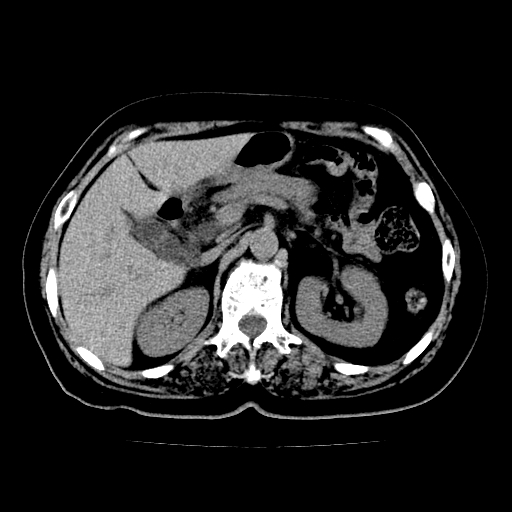

以下是引用zsl6918在2009-2-7 22:12:00的发言:[br]结合临床支持胰腺炎,建议强化查明胆总管扩张的原因。

以下是引用zsl6918在2009-2-7 22:12:00的发言:[br]结合临床考虑胰腺炎可能,建议强化查明胆总管扩张的原因。